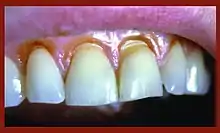

When looking at abfraction lesions there are generally three shapes in which they appear, appearing as either wedge, saucer or mixed patterns.[6] Wedge and saucer shaped lesions are the most common, whereas mixed lesions are less frequently identified in the oral cavity.[6] In reference to figure 1, wedge shaped lesions have the sharpest internal line angles and saucer/mixed shaped lesions are either smooth internally, or a variety.